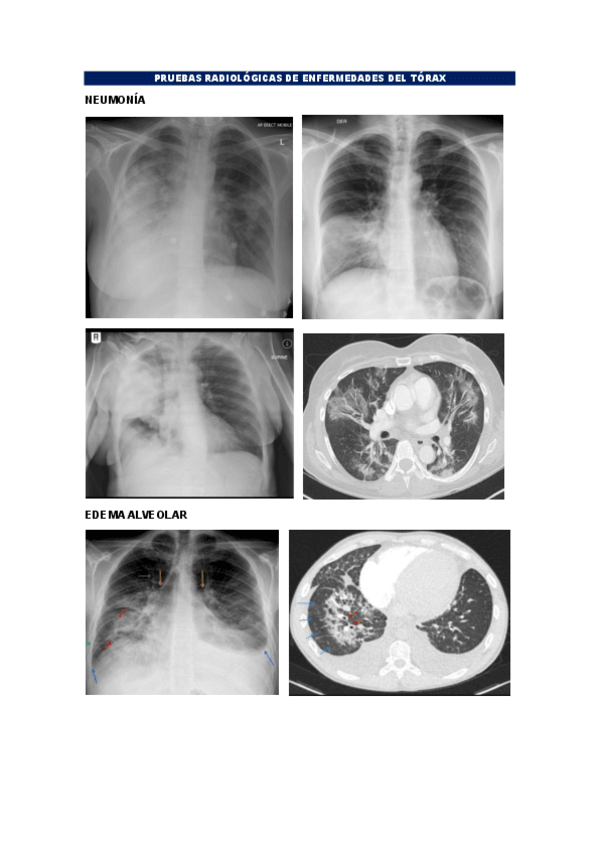

Ejemplos de RX, TC, RM de las enfermedades que hemos visto en clase o en prácticas. NO son fotos de clase ni de prácticas

BLOQUE-TORAX.pdf